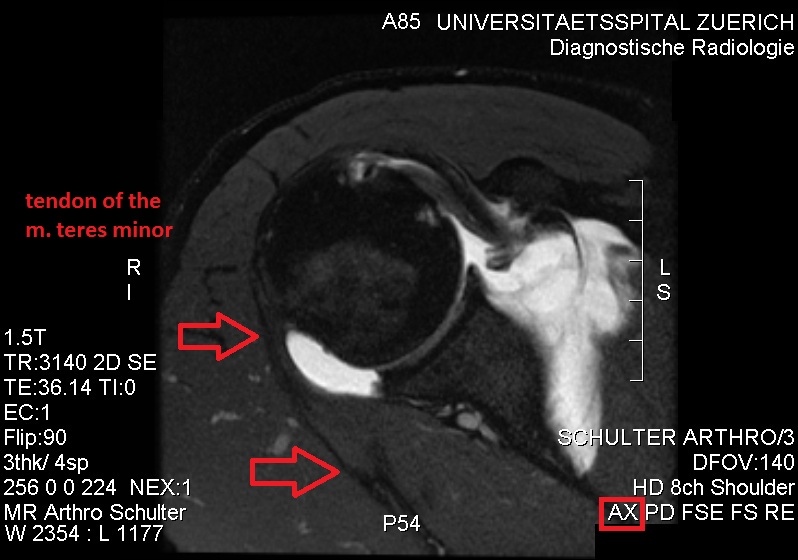

소원근과 극하근의 결합되고 손상되지 않은 힘줄 디스크.

생리학적으로 저신호 강도를 보이는 손상되지 않은 소원근 힘줄.

초음파검사(ultrasonography)는 소원근의 지방 퇴행성 위축을 탐지하는 도구이며, 다친 근육의 에코 발생(echogenicity)가 늘어나고 근육 부피의 약간의 감소가 보이기도 한다. 자기 공명 영상(MRI)는 신경성 근위축(neurogenic muscle atrophy) 진단에 유용하다. 외상 후 세포외수종(extracellular edema)은 신경 손상을 일으키며, MRI T2 강조 영상(T2-weighted MRI) 결과에서의 신호 강도(signal intensity) 증가와 T1 강조 영상 결과물에서의 신호 강도 정상을 보인다. 후방상완골선회동맥 압축과 스트레스를 유발하는 팔 위치나 조작으로 인한 혈류 감소는 도플러 초음파 검사(Doppler ultrasonography)로 진단할 수 있다. 혈관 옆 신경이 탐지된다. 팔을 들어올린 자세에서는, 액와신경혈관다발(axillary neurovascular bundle)이 삼각근을 관통하기 바로 직전에 후방 겨드랑 주름(posterior axillary fold)에서 보일 수 있지만, 팔을 내린 자세에서는 후방 코스(posterior course)가 잘 보인다. 동맥의 자세한 진단을 위하여, MR 혈관 조영술(MR angiography)이 필요하다. 초음파 검사는 무게를 갖는 공간을 탐지하는 것이다. 추가적인 근전도 검사(electromyography)는 신경 전도(nerve conduction) 속도 감소와 관련 근육의 신경 제거(denervation) 상태를 밝혀내는 데 유용하다.[12][6]